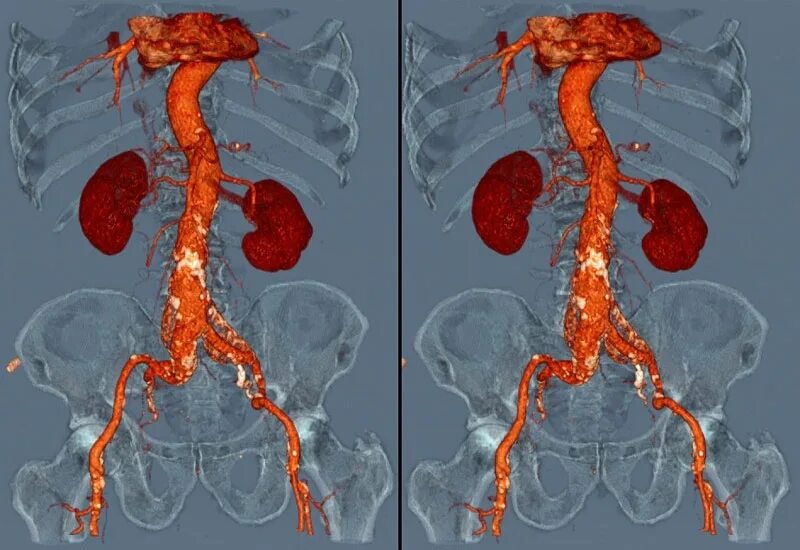

Как подготовиться к кт с контрастом почек